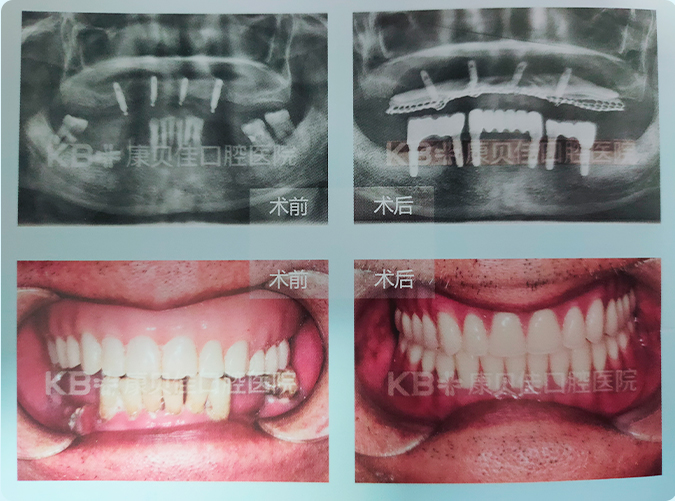

谢先生 74岁

常年备受口腔问题困扰,到院检查后发现不仅牙齿所剩无几,更重要的是牙槽骨萎缩严重、种植难度大。胡华分主任仔细分析后为谢叔叔定制了方案,通过添加骨粉骨膜+精准定位种植避开牙槽骨薄弱区域的方式顺利为谢叔叔种上了好牙。

治疗方案:

上颌4颗种植体恢复上半口 下颌6颗种植体恢复下半口